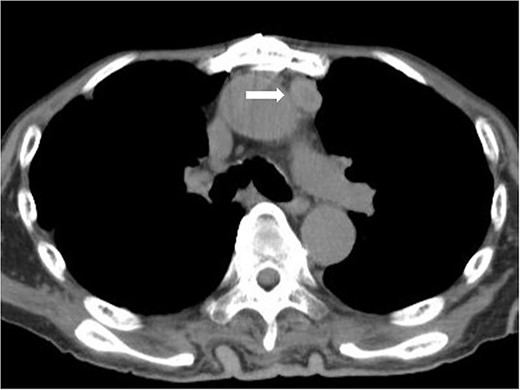

The patient was followed-up on an outpatient basis, without any additional chemotherapy or radiotherapy. On routine chest CT checkup after 18 months, lymphadenopathies were observed in the anterior mediastinum (Fig. 5), but no further investigation nor clinical intervention was intended on patient’s will. Twelve months later, he was diagnosed with nephrotic syndrome after he presented with sudden edema of the lower limbs. Although he recovered from the nephrotic syndrome after administration of corticosteroids, he suffered a traumatic spinal injury due to an accidental fall from the hospital bed. He finally died at home from respiratory failure 30 months after the surgery.

Chest CT scan 18 months after surgery. Mediastinal lymph node recurrence was suspected.